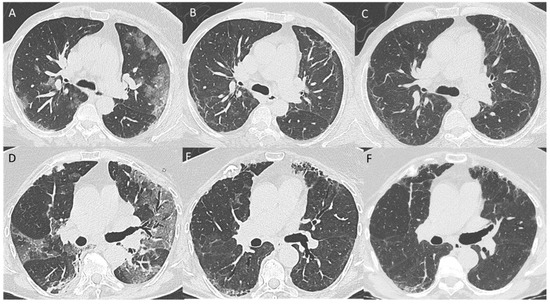

3.2. 5–7-Month Follow-Up CT Scan

3.4. Pattern Evolution